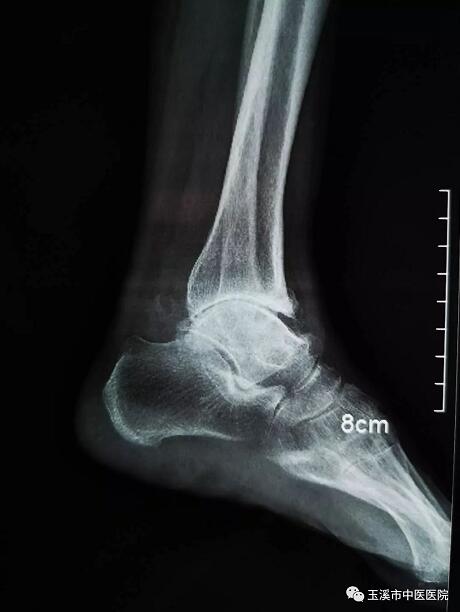

在醫(yī)務(wù)人員緊張的情況下,骨傷Ⅰ科克服種種困難,先后派出3名一線醫(yī)務(wù)人員赴千里之外的德欽縣人民醫(yī)院進(jìn)行對(duì)口援助。朱金富醫(yī)生是今年8月份去到藏區(qū)的,一到那里便積極投入工作。一位五十六歲藏族阿媽來到醫(yī)院看病時(shí),左踝關(guān)節(jié)疼痛、畸形三十余年了。 朱醫(yī)生將她收治入院,在相關(guān)檢查后,為她做了左踝關(guān)節(jié)融合術(shù)。術(shù)后藏族阿媽左踝關(guān)節(jié)功能明顯改善,生活及勞動(dòng)能力有所恢復(fù),一家人皆大歡喜。

術(shù)前X光片(左踝關(guān)節(jié)側(cè)位)